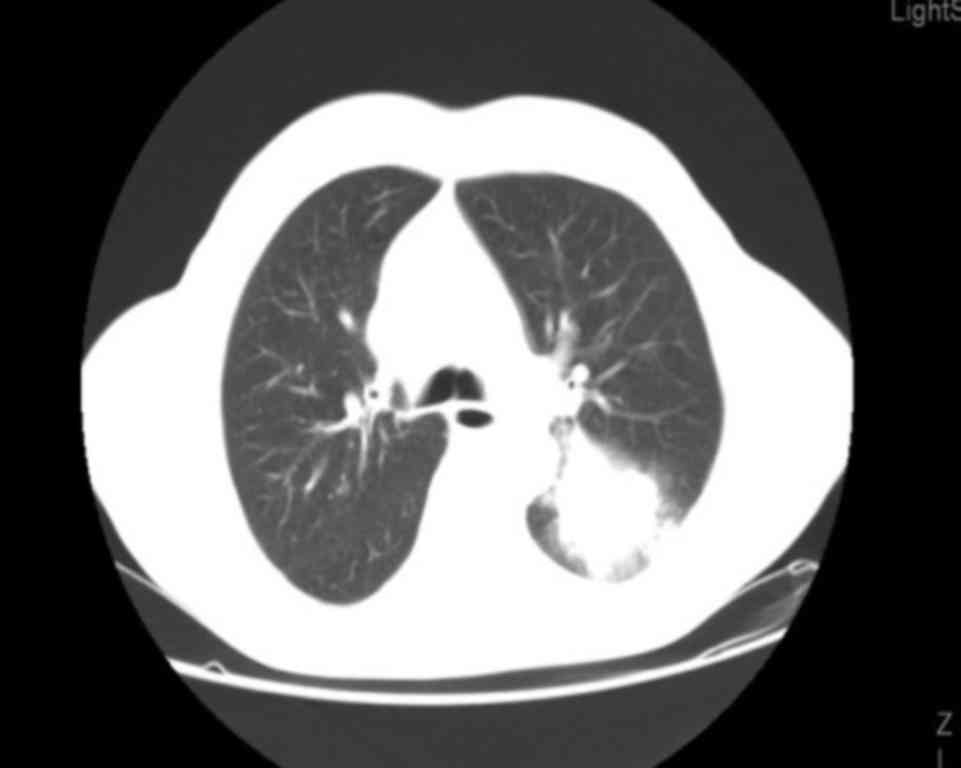

Long-term survival in a patient with metastatic squamous cell lung carcinoma: A case report

Non-small-cell lung cancer (NSCLC) is the most common malignancy in industrialized countries, with a 5-year survival rate of only ~15%, as the majority of the patients have advanced-stage disease at diagnosis and the treatment options are limited. Squamous cell carcinoma the second most frequent type of NSCLC and is closely associated with cigarette smoking. We herein present the case of a 72-year-old male smoker, diagnosed with stage IV squamous cell lung carcinoma, with a solitary brain metastasis. After the diagnosis, stereotactic radiotherapy was performed on the brain metastasis. Following radiotherapy, chemotherapy with carboplatin + paclitaxel was initiated. However, after 2 cycles of chemotherapy, disease progression in the lung was observed. Therefore, second-line treatment with pemetrexed was started, which was discontinued after 2 cycles due to further disease progression. Third-line treatment with erlotinib was then administered, with notable benefit, as the patient remains alive after 6 years of treatment with a good performance status. The mutation status of EGFR was unknown.

Figure 1

Figure 2

Figure 3

Figure 4